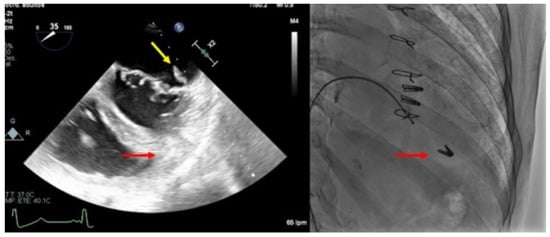

TEE allows us to study the basal mitral area (which must be at least more than 4 cm2), and the mobility, flexibility, and thickness of the leaflets in order to avoid significant mitral stenosis when one or more clips are implanted. Likewise, TEE is essential in the evaluation of the appearance of mitral stenosis after grasping. Medium gradients greater than 5 mmHg are not acceptable since they have been related to worse outcomes [19] (Figure 3). When this happens, the grasping must be carried out again to try to avoid the stenosis, and the implant must be abandoned when this is not possible.

Figure 3.

Severe mitral stenosis after implantation of a mitral clip measured by Doppler echo.